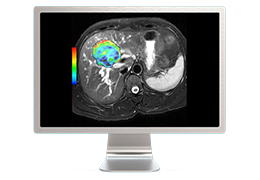

View X-Ray CT & MRI Scans Fast and Easily

Designed for surgeons, Pro Surgical 3D makes it easy to view patient scans quickly. Pro Surgical 3D facilitates the optimal 3D treatment and assessment workflows based on X-ray CT and MRI scans – and best of all, it’s FREE!

Everyone – including surgeons, patients and their loved ones – benefits from being better informed by the wealth of information buried within CT and MRI scans. Pro Surgical 3D gives surgeons more information to develop optimal treatment plans for patients. It also helps patients and their support group better understand their medical condition and proposed treatment options.

Designed mainly for CT and MR DICOM modalities.

Performs 3D reconstruction and volume rendering.